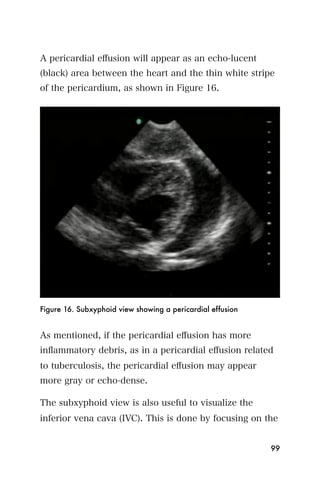

A pericardial effusion will appear as an echo-lucent

(black) area between the heart and the thin white stripe

of the pericardium, as shown in Figure 16.

Figure 16. Subxyphoid view showing a pericardial effusion

As mentioned, if the pericardial effusion has more

inflammatory debris, as in a pericardial effusion related

to tuberculosis, the pericardial effusion may appear

more gray or echo-dense.